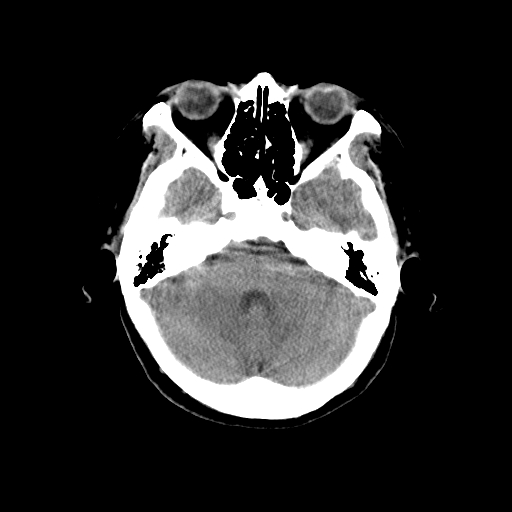

标题: CT14513:女性41岁,头部不适二月余,其它病史不详。请分析 [打印本页]

标题: CT14513:女性41岁,头部不适二月余,其它病史不详。请分析

考虑ii-iii级星形细胞瘤可能性大。

1.考虑:左侧颞顶叶星形细胞瘤。2.大脑镰下疝。

支持!但楼主所提示处颅骨明显受压变薄,是否有合并蛛网膜囊肿或局部硬膜下水瘤的可能?脑穿通畸形暂不予以考虑:明显占位表现;病侧脑室无扩张;病灶不是较明确的脑脊液密度;边界不清晰。还是mri检查吧,提供的有价值信息更多一些,至少可以排除或肯定蛛网膜囊肿或局部硬膜下水瘤的存在。